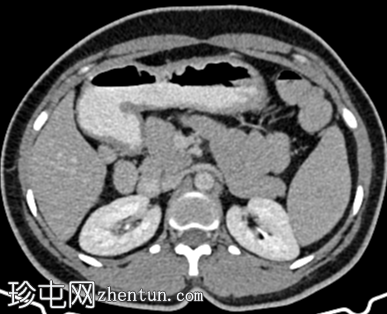

CT

轴位

平扫

脾脏内可见一圆形低密度病灶,动脉期呈周边环状强化,延迟期呈轻微向心性充盈

未见钙化、动静脉畸形或动脉瘤